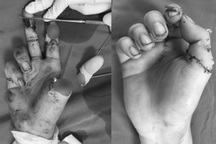

Bệnh nhân bị hoại tử ngón tay sau khi bị điện giật (Ảnh: Bệnh viện cung cấp).

Bệnh nhân bị tổn thương hoại tử khô toàn bộ mặt gan ngón V, một phần gan ngón IV, kẽ ngón IV-V.

Tổn thương không đi kèm tổn thương xương, nhưng lại bị co kéo, chảy dịch mủ hôi, đau nhức nhiều dẫn đến mất vận động ngón V, ảnh hưởng đến sinh hoạt và cuộc sống.

Sau khi hội chẩn chuyên môn với các chuyên khoa và làm các xét nghiệm cận lâm sàng chuyên sâu, các bác sĩ nhận thấy đây là một trường hợp tổn thương rất phức tạp do điện giật, hoại tử ngón tay, lại đang có nhiễm trùng tổ chức nặng.